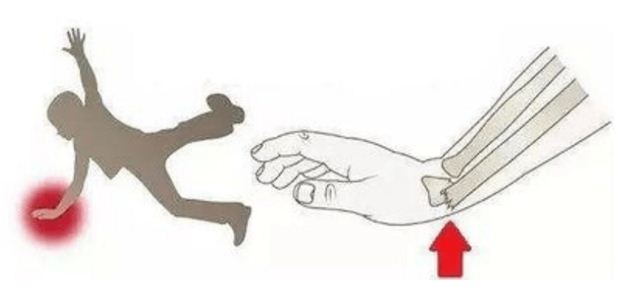

病例一 病例二 科 普 时 间 什么是桡骨远端骨折? 桡骨远端骨折的症状? 桡骨远端骨折如何治疗? 专家推荐 原志红 【专业特长】 从事临床工作20余年,擅长心肺复苏、创伤骨科的处理,以及各种复杂的四肢骨折、关节损伤等疾病的诊治,在急危重症患者的抢救治疗方面有丰富的临床经验。 山西省“百千万卫生人才培养工程”骨干精英人才、山西省专家学者协会骨科专业委员会常务委员、山西省医师协会急诊委员会委员、山西省创伤联盟创伤学组委员、长治市骨科专业委员会委员、长治市劳动能力鉴定中心专家组成员、长治市医师协会急诊医师分会副会长、长治市急诊专业委员会副主任委员、长治市健康协会重症医学专业委员会委员。 医生推荐 从事骨科创伤工作十余年,擅长四肢骨折、关节脱位、高坠伤、机械伤等各类创伤救治,对于各种急危重症有丰富的临床经验,2023年9月于郑州大学第一附属医院急救中心完成进修学习。 科室简介 急诊医学科成立于1985年,是长治地区成立较早的急诊急救专科科室之一,肩负着本院及周边地区急、危、重症病人的急救任务。 现拥有急救专业人员29名,包括主任医师2名,副主任医师2名,主治医师6名,住院医师3名;主任护师2名,副主任护师1名,主管护师5名,护师8名。经过多年的发展,科室现已发展成为一所设备先进、技术精湛、功能完善的现代化急诊急救科室,在急腹症、骨科创伤特别是批量伤员的救治方面,因人员配置合理、技术力量雄厚、急救模式规范、绿色通道畅通而处于上党地区先进地位。 急诊医学科设有分诊台、抢救室、诊疗室、留观室、手术室、急诊放射、心电图和B超等多个区域,这些区域布局紧凑,流向合理,均有醒目的标志及引导指示标牌,有利于急诊病人就诊。急诊医学科同时承担长治市120急救任务,为了进一步降低病人死亡率、伤残率,我们有特色的现场急救一途中转运一急诊室一病房、重症监护室的绿色生命通道急救模式,以最快速度将急需治疗设备和技术送至危重病人现场,维持生命,维持转运途中安全。 新起点新征程,在医院跨越式发展的浪潮中,长治二院急诊医学科正朝着现代化的一流急诊急救中心方向大步迈进。 急救专线:0355—96220 供 稿丨何 龙 编 辑丨谌飞君 审 核丨雷 赫